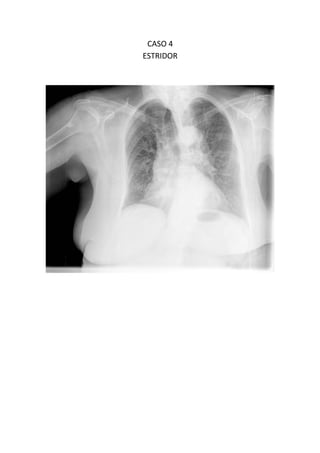

Este documento presenta 7 casos de patología torácica que serán discutidos en una sesión de interpretación radiológica. El objetivo es que los asistentes tomen notas aclaratorias durante la discusión interactiva de cada caso, en lugar de una mera explicación teórica. Los casos incluyen agenesia pulmonar derecha, situs inversus, estridor, neumonía con hemoptisis y enfermedad intersticial. El último caso involucra a un paciente de 86 años con tos y disnea que podría tener una consolidación en la base